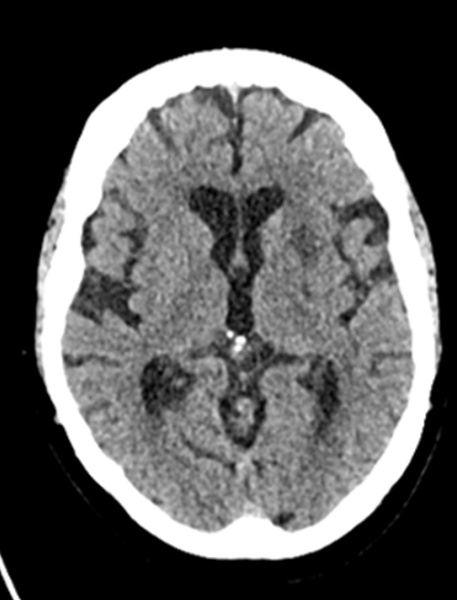

Baseline CT - ASPECTS 10

Baseline CT MCA hyperdensity

• Follow-up CT showed no hemorrhagic transformation, with only a small established deep left infarct